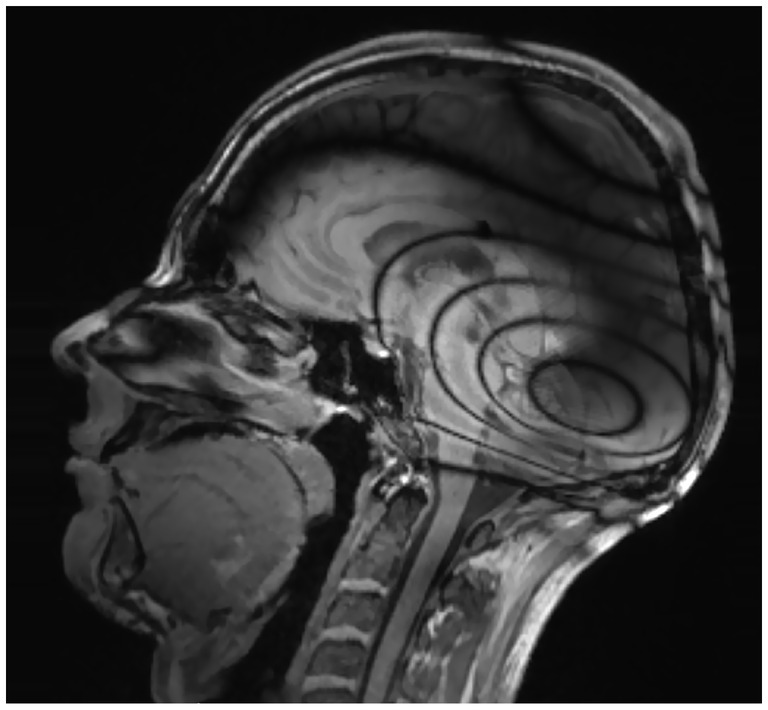

Nasopharynx

In cases of ipsilateral CI (with and without the magnet in situ), the nasopharynx was clearly assessable in the performed sequences [T1-MP-RAGE, T2-TSE, T1-TIRM (Table 2)]. On the contralateral side, the nasopharynx was evaluable in all conditions and sequences. However, with bilateral CIs and the magnet in situ, the nasopharynx was not fully assessable due to artifact overlap (see Figure 4). After magnet explantation, visibility was restored. DWI was not assessable at all for the nasopharynx with magnet in situ for ipsi- and contralateral CI condition in all three examined angular positions. The sphenopalatine foramen/pterygopalatine fossa was visible in the ipsilateral CI condition but not in the bilateral CI condition.

Figure 4

T1-weighted sequence in a bilateral CI with a magnet positioned at a 135° angle demonstrating that the nasopharynx is only partially assessable.